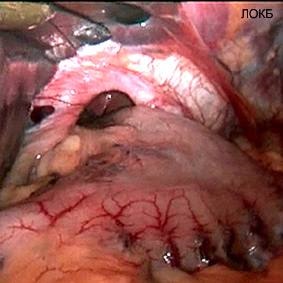

Cel mai recunoscut astăzi baza pentru punerea în aplicare a chirurgiei antireflux este dezvoltarea simptomelor de GERD la pacientii cu hernie hiatala (hernie hiatală, fig. 1, 2).

Figurile 1 și 2. hernie hiatală - cauza bolii de reflux gastro-esofagian (foto intraoperator)

Schimbarea relațiilor anatomice naturale în zona de tranziție gastroesofagian se referă la cele mai frecvente cauze ale unei defecțiuni mecanice a sfincterului esofagian inferior. Boala cauza organica predetermină un impact redus asupra eficienței chimioterapeutic diferitelor sale simptome. Pe de altă parte, manifestările minime de reflux gastro-esofagian, care apare pe fondul unei hernie hiatala, în multe cazuri, modificări simple, care pot fi supuse la modul de corectare sau terapia standard. Astfel, o abordare echilibrată la determinarea indicațiilor pentru tratamentul chirurgical al GERD, condiționate (sau agravare) hiatala hernie, trebuie să țină seama de gravitatea manifestărilor clinice ale bolii de reflux gastroesofagian și complicațiile sale. Motivul pentru efectuarea reconstrucției este esofagian antireflux rezistență (sau vnepischevodnyh) manifestări ale bolii la tratamentul medicamentos. efectul acut al tratamentului conservator, nevoia de utilizare continuă a medicamentelor antisecretorii, și în special apariția complicațiilor, sunt în prezent considerate ca indicii obiective pentru o intervenție chirurgicală.